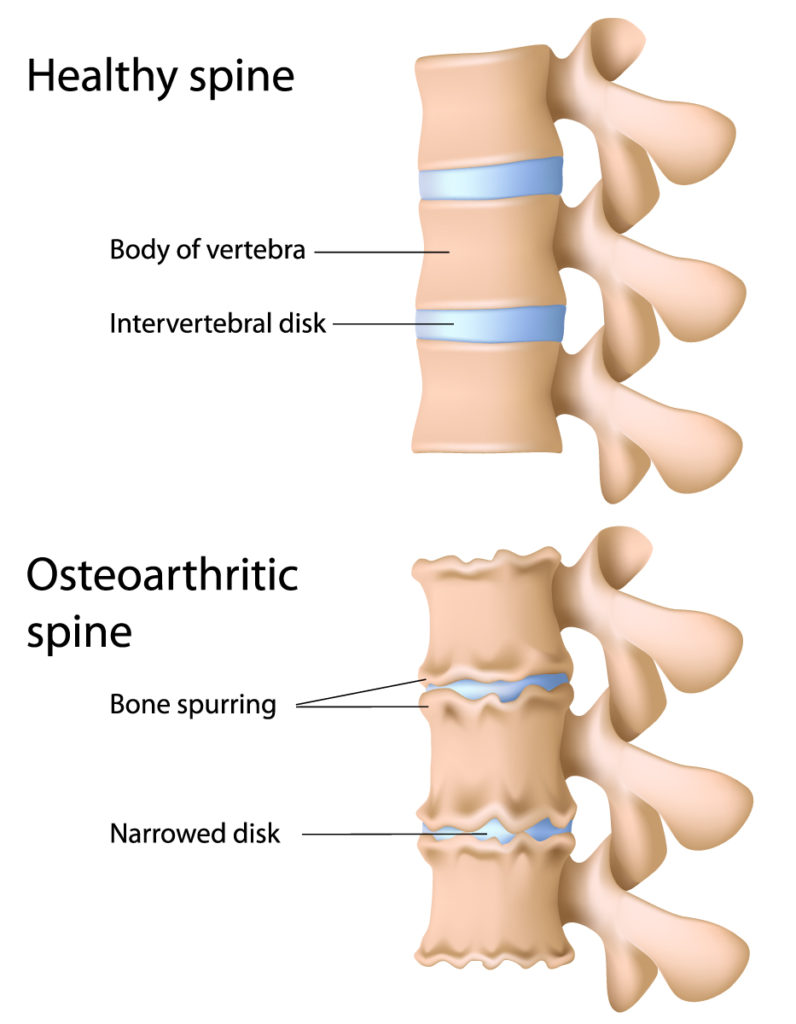

Osteoarthritic Spine

The image presents a comparison between a healthy spine and an osteoarthritic spine.

In the top half, the healthy spine is depicted with well-defined and uniformly shaped vertebral bodies. The intervertebral discs, the cushion-like pads between vertebrae, are intact and maintain a consistent height, allowing for proper spacing between the vertebral bodies. These discs are essential for absorbing shock, providing flexibility, and maintaining the integrity of the vertebral column.

In contrast, the bottom half illustrates an osteoarthritic spine. Osteoarthritis is characterized by the breakdown of cartilage and can affect any joint, including those in the spine. The vertebral bodies show signs of bone spurring, also known as osteophytes, which are bony projections that form along joint margins. These growths can occur as a natural response to the increased pressure on the degenerating cartilage and can contribute to the stiffness and pain commonly associated with osteoarthritis. Additionally, the intervertebral discs are narrowed, indicating disc degeneration. This narrowing can lead to reduced flexibility, potential nerve compression, and changes in the structure and stability of the spine.

Overall, this image serves to illustrate the structural changes that occur in the spine due to osteoarthritis, highlighting the contrast between a healthy and an affected vertebral column.